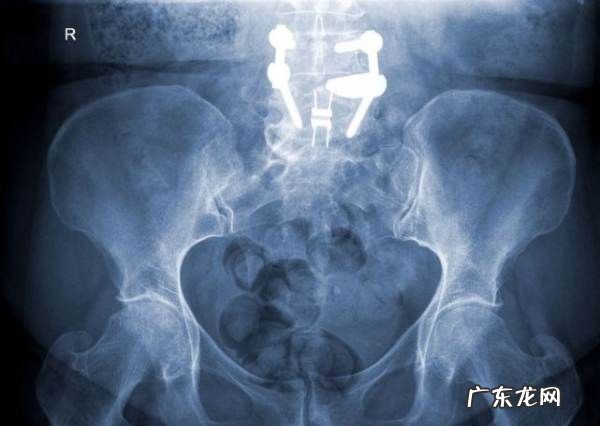

1.腰椎X线检查可宏观地观察腰椎退变或外力损伤情况,对腰椎退变性滑脱、腰椎间盘退变性椎间隙变窄、移行椎、骨折、骨肿瘤等疾病,X线检查均有重要的诊断意义,结合临床可直接诊断马尾神经损害 。

怎样检查出马尾椎神经受损腰椎X线平片检查:

腰椎X片可宏观地观察腰椎退变或外力损伤情况,是腰椎疾患诊断的基础,尤其是确定马尾神经的病因X线片不可忽略 。腰椎间盘退变性椎间隙变窄、移行椎、骨肿瘤等疾病的X光片均有重要的诊断意义,结合临床可有效诊断马尾神经损伤 。